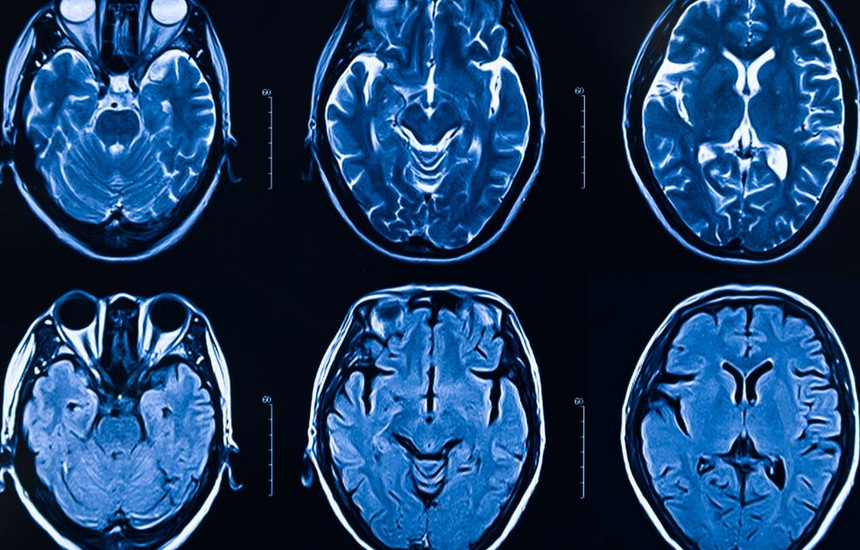

Si e sulmon koronavirusi trurin?

Koronavirusi prek mushkëritë në përgjithësi, por gjithashtu edhe veshkat, mëlçinë dhe enët e gjakut. Prapëseprapë rreth gjysma e pacientëve kanë simptoma neurologjike, përfshirë dhimbjet e kokës, tendosjen dhe hutimin, duke bërë të ditur se virusi mund ta sulmojë edhe trurin.

Një studim i ri ofron provën e parë të qartë se, në disa njerëz, koronavirusi pushton qelizat e trurit, duke i rrëmbyer ato për të bërë kopje të vetvetes. Virusi duket se edhe e thith të gjithë oksigjenin afër, duke shkaktuar vdekjen e qelizave fqinje.

Është e paqartë se si virusi arrin në tru dhe se sa shpesh nis këtë provim të shkatërrimit. Infektimi i trurit ka të ngjarë të jetë i rrallë, por disa njerëz mund të jenë të ndjeshëm për shkak të prapavijës së tyre gjenetike, një ngarkesë e lartë virale apo arsye të tjera.

Në studimin e tij, Dr. Iwasaki dhe kolegët e saj dokumentuan infektimin e trurit në tri mënyra: në indet e trurit nga një person që ka vdekur nga COVID-19, në një model miu dhe në organoide – grumbujt e qelizave të trurit në një pjatë laboratori duhej ta imitonin strukturën tredimensionale të trurit.